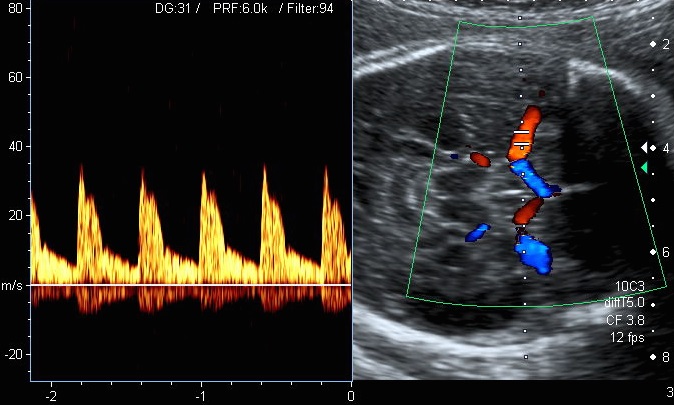

Dopplersonographie

Die Dopplersonographie ist ein Untersuchungsverfahren mit dem der Blutfluss in mütterlichen und kindlichen Gefäßen dargestellt und beurteilt werden kann. Außerdem kann eine Aussage zur Durchblutung und Funktionsfähigkeit einzelner Organe gemacht werden.

Die dopplersonographische Untersuchung bestimmter kindlicher Gefäße gibt Informationen über die Versorgung und den Zustand des Kindes. Diese Untersuchung ist insbesondere dann notwendig, wenn sich Anzeichen einer kindlichen Störung (z.B. Wachstumsverzögerung) zeigen. Auffällige Blutflussmuster können Hinweise auf eine kindliche Gefährdung sein, die eine vorzeitige Entbindung nötig machen.